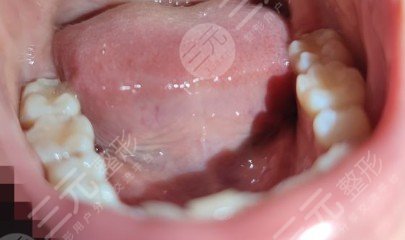

在深圳市公立口腔医院整牙一开始很漫长,也很犹豫,但是想到与长相有关的牙齿,就很重要了。然后我的牙齿有一颗门牙被挤出来很多,还有一些下牙被挤出来。有的是凹的,凹凸不平的不好看~我选择了经济型的金属自锁牙套,希望能GET理想的矫正果~我很开心,我以为牙齿这么短的时间不会有变化。然而,单看牙齿的变化就相当明X了。上面挤出来的牙明X是内收的,下面挤出来的牙也是内收的,旁边歪牙整齐多了。我很开心~我越来越期待整牙的样子。

这一个月,下牙已经基本排整齐了。较近一个月掉了两个托槽,因为上下被咬掉了,医生说要给我,加点东西,有点紧张。其他什么都没有,所以清理一下口腔,及时复诊,配合好就够了。~牙齿已经基本排好了,所以下一步应该是闭上牙齿。这比我没有排时想象的要快。但是,这次又去深圳市公立口腔医院,医生说我的下牙太高了,压不下去。戴牙套还有很长的路要走。

牙齿已经排好,现在已经进入封缝阶段。经过上个月的调整,差距稍微小了一点,但是侧面摄像头的唇还是凸起的,牙齿的中心线也不整齐。深圳市公立口腔医院医生表示继续调整很正常,所以继续调整~还是期待较终果。这个月,很明X前排上下牙齿的牙缝都被拔掉了,下牙齿的牙缝继续向内,上排的牙齿比较慢,因为牙龈暴露严重,下个月需要把牙龈拉上来。